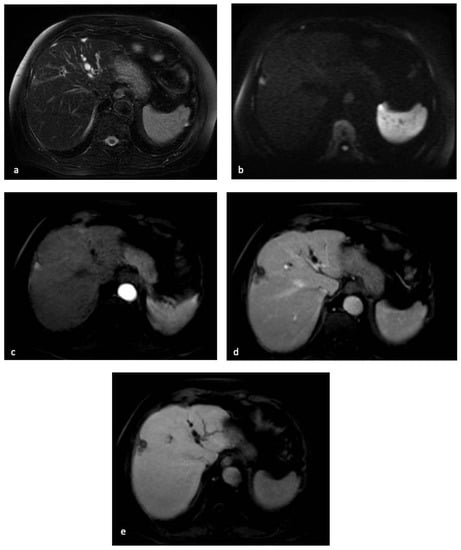

Since up to 90% of HCCs demonstrate hypointensity in the HBP, this ancillary feature may contribute to the differentiation of HCC from benign nodules developed in chronic liver diseases (Figure 3) [87].

MR examination of the patient discussed in Figure 1 and Figure 2. On T2-weighted images, the centimetric subcapsular appeared as hyperintense (a). On DWI with a b-value of 1000, the lesion showed signal restriction (b). After administration of a hepatobiliary contrast agent, the lesion showed arterial hyperenhancement (c) with hypointensity in the portal-venous phase (d) and in the hepatobiliary phase. (e) The lesion appeared hypointense.

However, until now, there has been no established consensus regarding the value of HBP hypointensity during liver MRI. In East Asia, some guidelines attribute importance to the use of HBP hypointense appearance, thus permitting the diagnosis of smaller HCCs [88]. Meanwhile, in the Western countries, where liver transplantation is one of the major treatment options [89], the practice guidelines suggest that wash-out should be determined in the portal phase, thus obtaining the highest specificity [12]. In fact, recent studies have suggested that HBP hypointense appearance is highly sensitive and specific for HCC when combining with non-rim APHE [84].